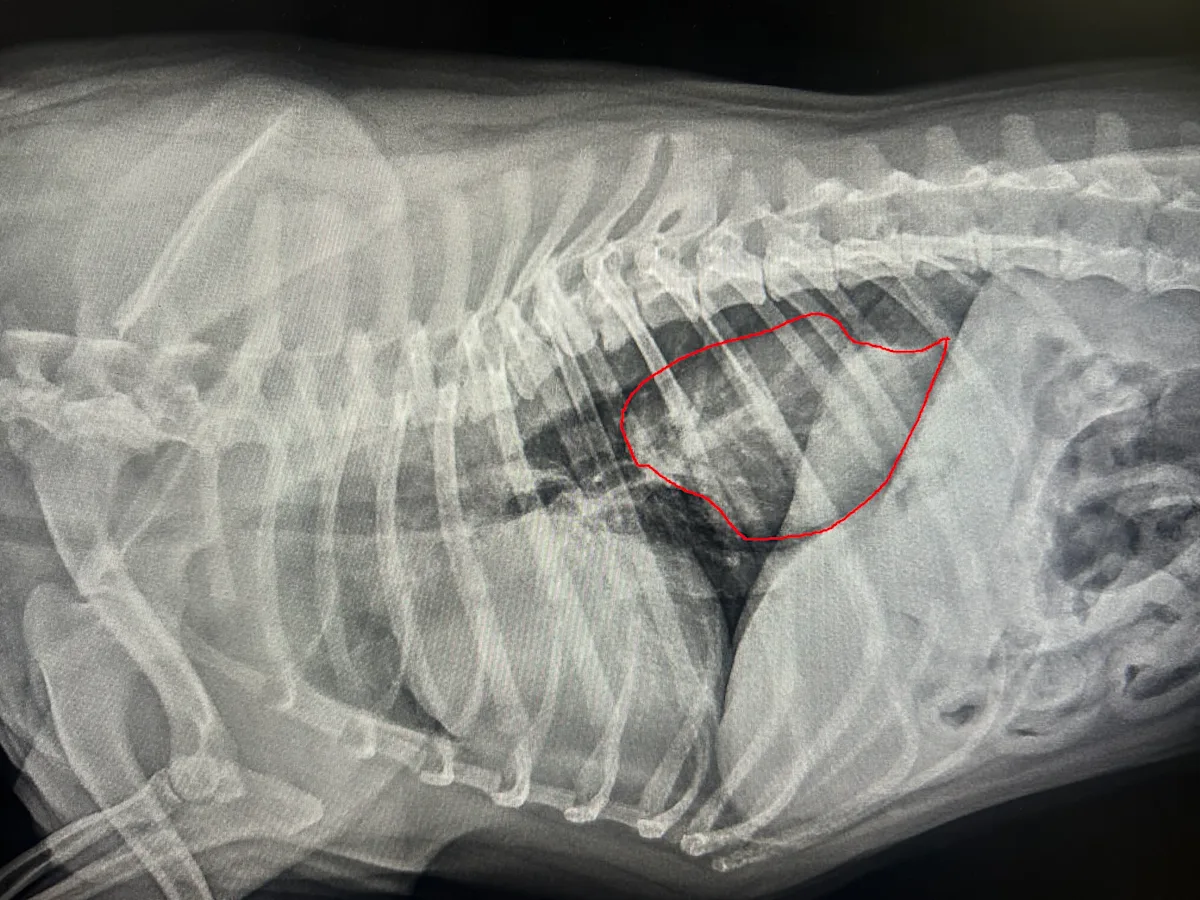

Examine this lateral thoracic radiograph to identify a hiatal hernia in a 3-year-old French bulldog, and learn the radiographic clues that distinguish it from masses or foreign bodies.